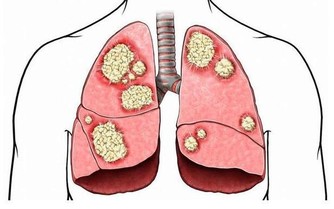

蘑菇中含有大量的硒元素,而硒是人體必須的微量元素,

可以提高人體的免疫力,補硒是人們預防肝癌、防治肝病的有效措施。

蘑菇中含有豐富的硒元素,易被人體吸收,是肝癌、腸胃癌等強有力的抑製劑,

所以我們日常生活中可多食用蘑菇。